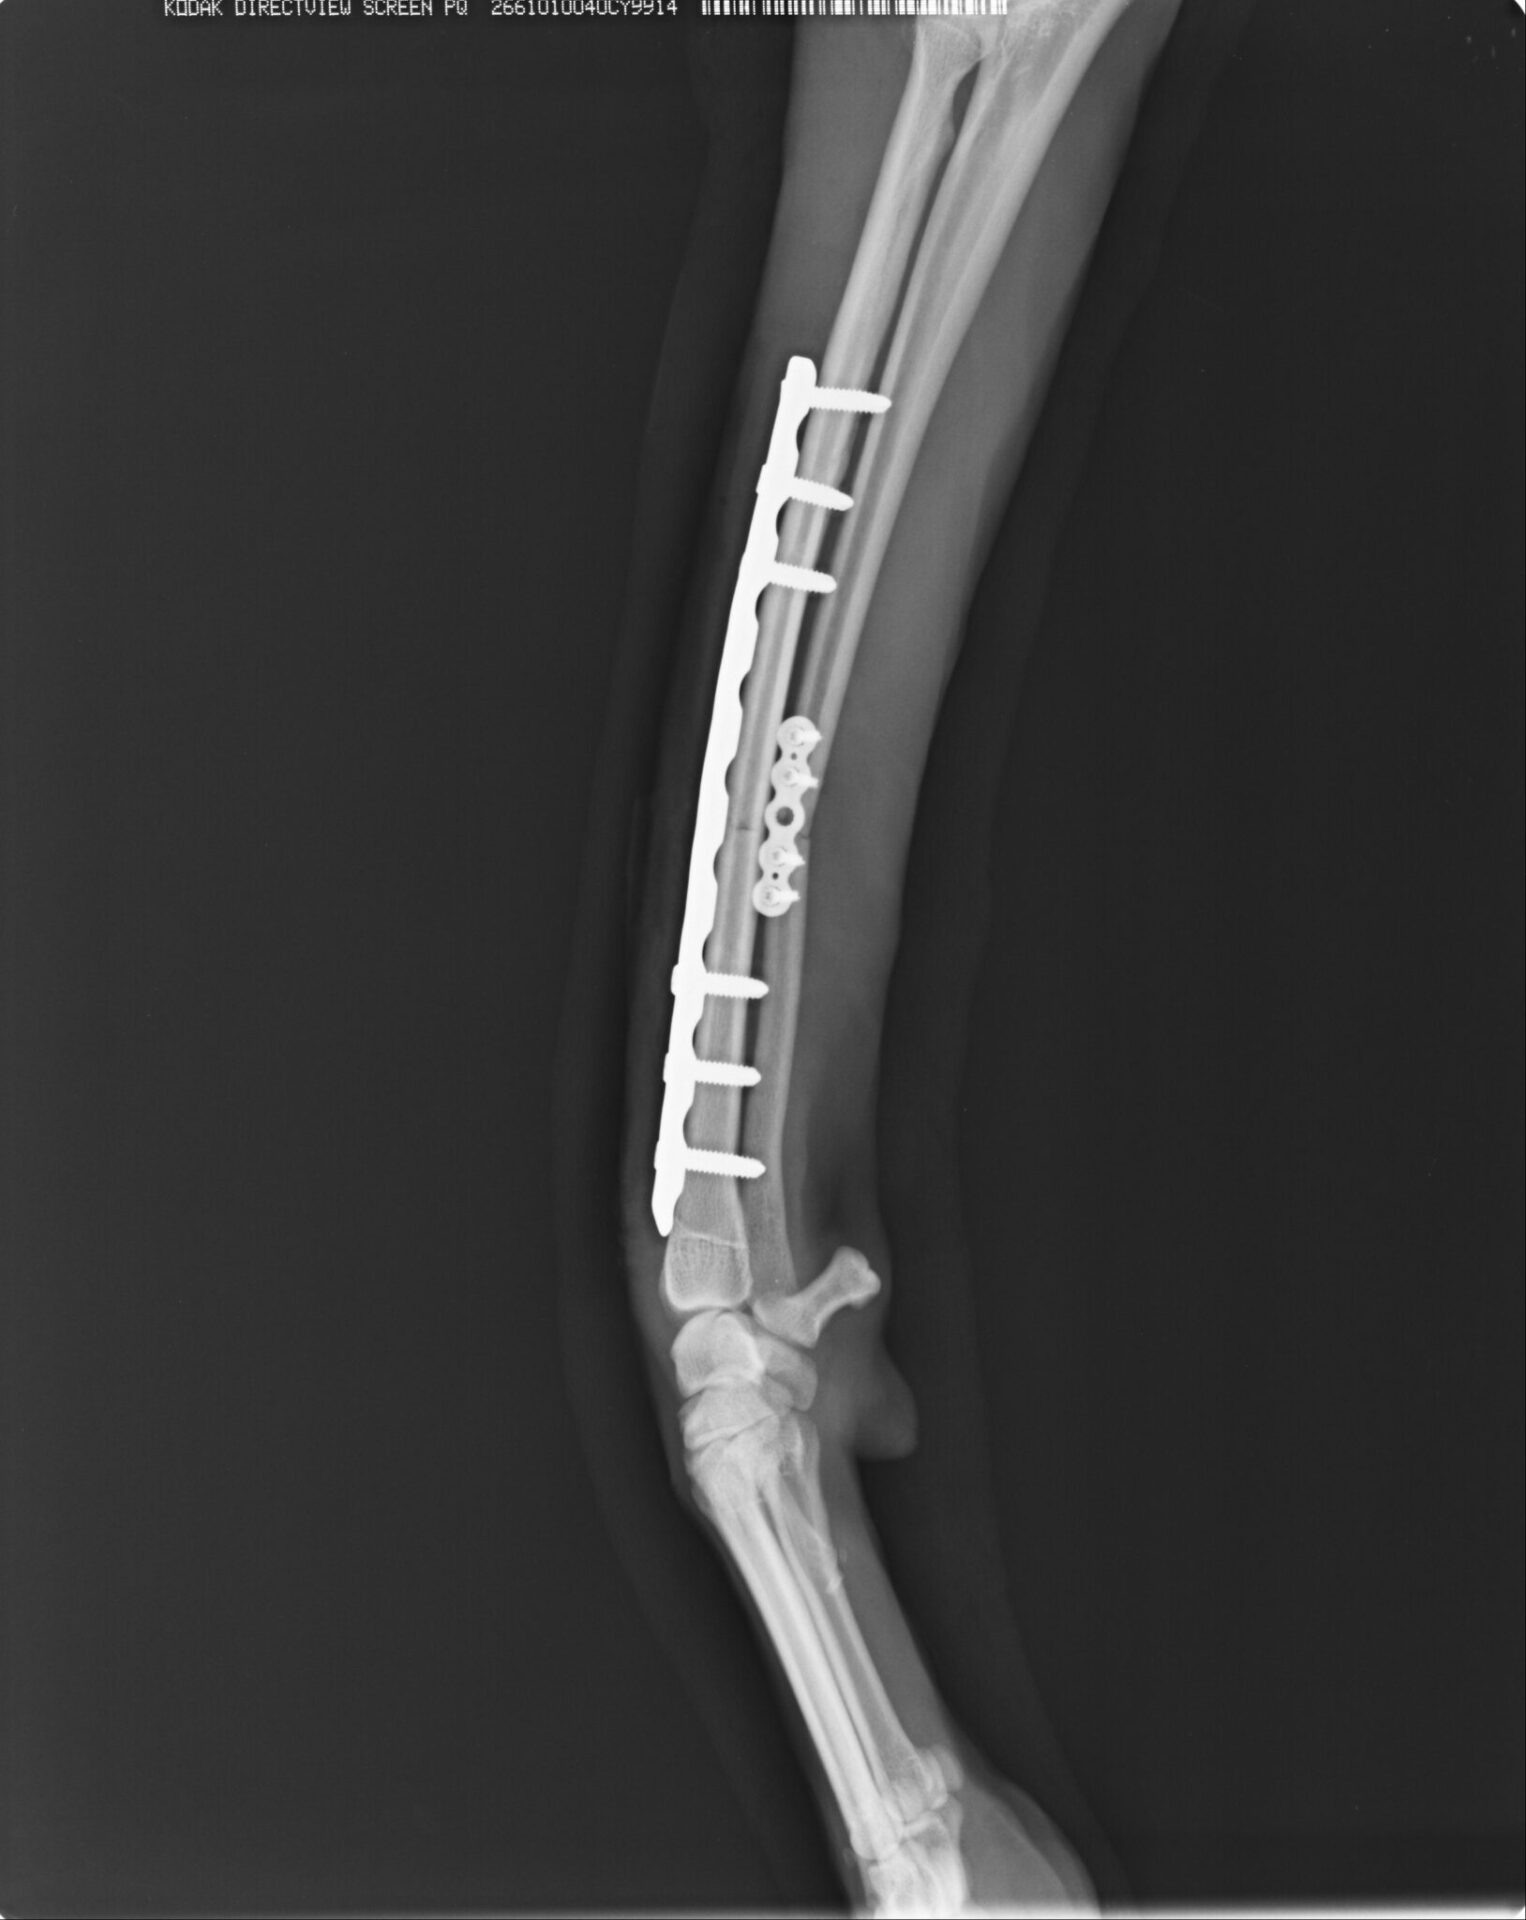

前腕骨骨折整復(ロッキングシステム)

強固かつ骨折修復過程に必要な組織を温存させた手術は治癒過程が早く、早期に運動を再開できます